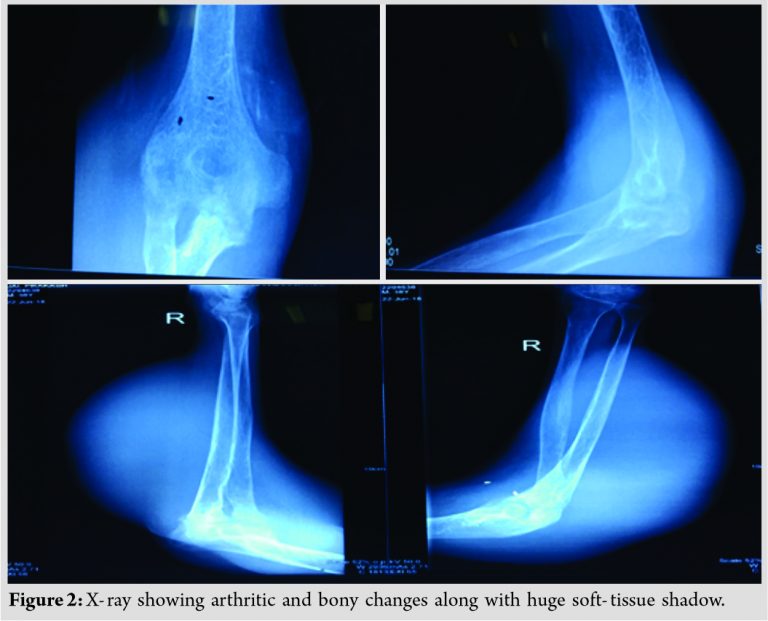

Distal neurovascular status was intact. Blood picture revealed raised lymphocyte count with raised erythrocyte sedimentation rate. Radiologically, X-ray of elbow joint showed arthritic changes along with multiple ill-defined no sclerotic lytic lesion involving humeral condyles, olecranon process of ulna, and radial head along with large soft-tissue shadow (Fig. 2).